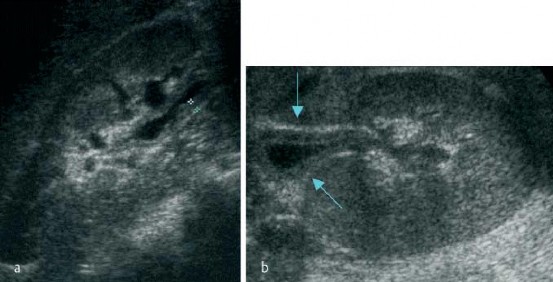

Hình 1.3. Hình ảnh dày thành bể thận (mũi tên) trong VTBT

(Nguồn: Mitterberger M. và cs, 2007) [124]

a: Mặt phẳng cắt dọc b: mặt phẳng cắt ngang